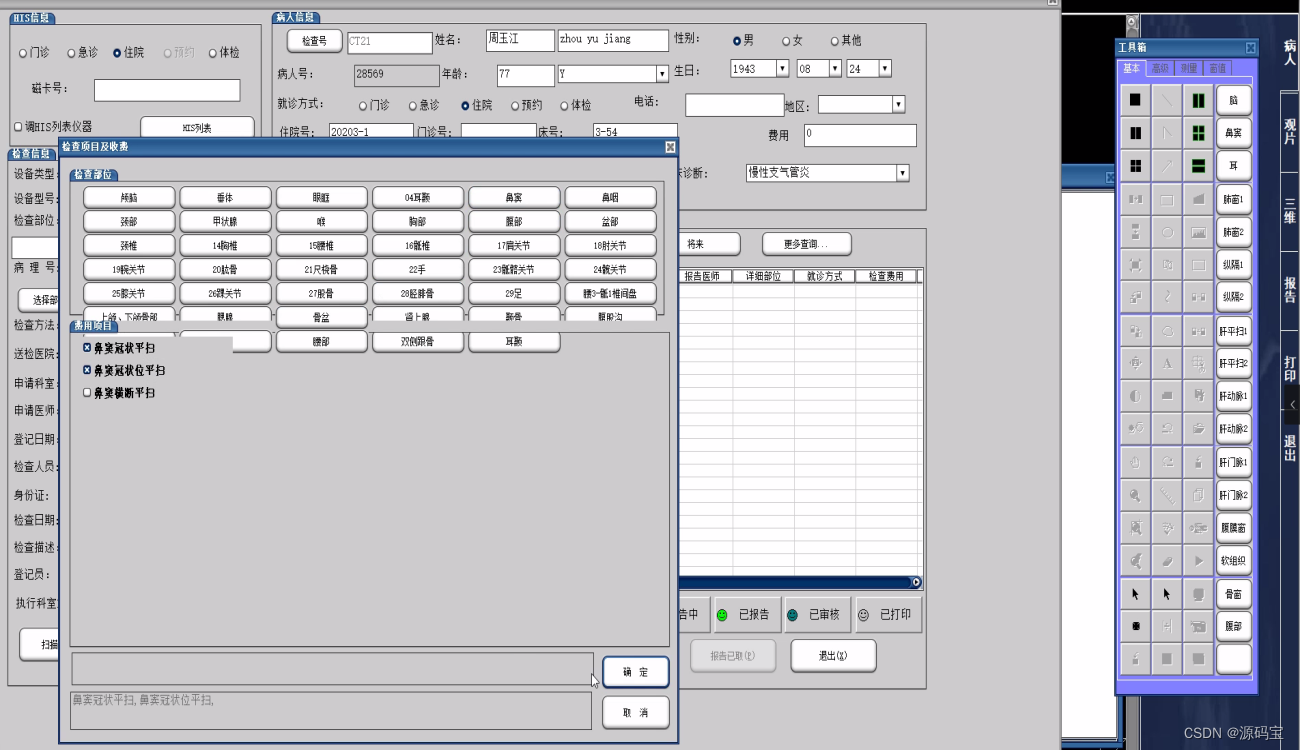

(1)申请与预约登记

支持刷卡从HIS系统获取病人信息功能,支持磁卡、IC卡、条码输入、手工输入。

支持电子申请单、扫描纸质申请单。

具有收费管理功能。

支持打印预约申请单、支持打印条码。